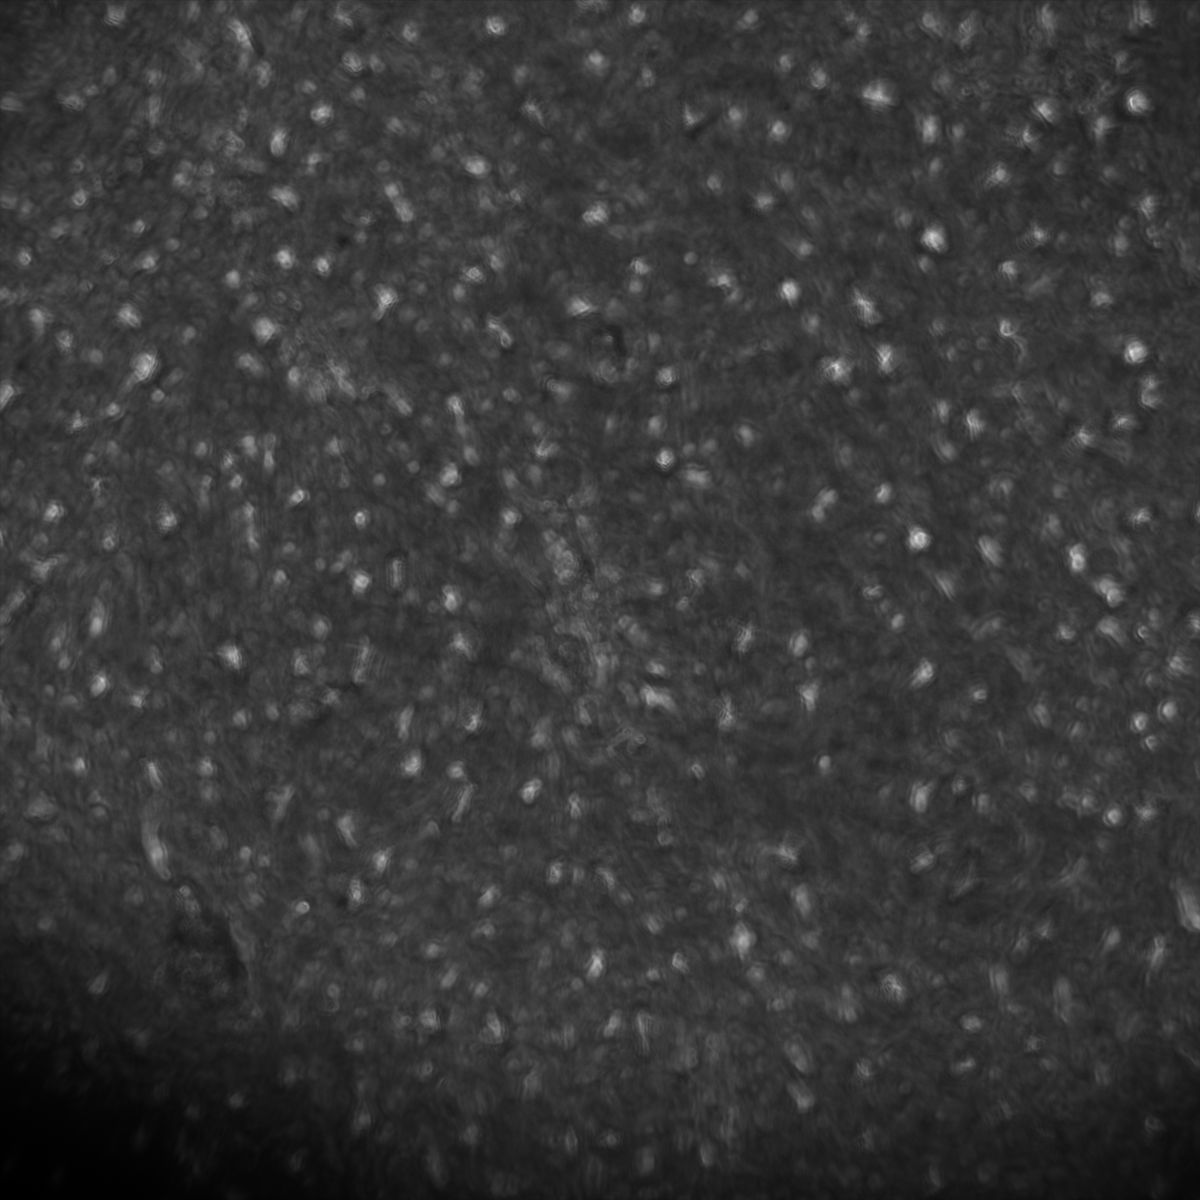

Healthy Choroid

Unhealthy Choroid